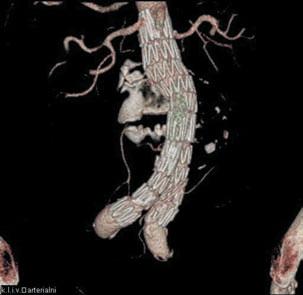

Aortální CT-angiografie je metodou volby (spolu s MR v některých indikacích). Je přesná s velkým rozsahem (od aortálního oblouku po femorální tepny). Vyšetření je možné doplnit kalibrací cév při plánování další intervenční léčby (například implantace stentgraftů do aneuryzmatu). Při požadavku na zobrazení pouze ascendentní aorty se s výhodou používá EKG triggering, který odstraňuje pohybové artefakty pulzující aorty. Mnohem lepší informace než při DSA jsou získány u disekce – průkaz entry a reentry, trombóza falešného lumina, zasahování do aortálních větví, ischemie orgánů. U aneuryzmat je možné přesně stanovit trombózu vaku a změřit jeho velikost. U typických případů se lze vyjádřit i k etiologii (ateromatóza, zánět, trauma). Sledujeme rovněž eventuální krvácení z vaku. Mezi další patologie indikované k zobrazení patří koarktace, posuzuje se její významnost, lokalizace, kolaterální oběh a další anomálie (perzistence d. Botalli). Častým nálezem jsou variace tepen odstupující z aortálního oblouku nebo variace aorty samotné. Při pooperačních vyšetřeních se sledují anastomózy aortálních náhrad, disekce, pseudoaneuryzmata, okolí aorty (obr. 1.7).